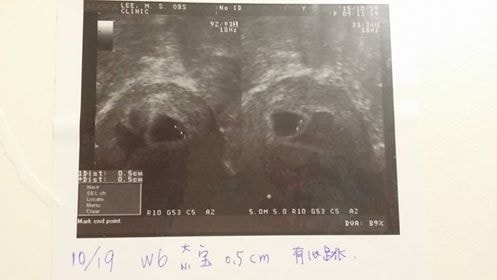

20151014-DAY24-46KG兩寶胚胎5W+這幾天的胃不舒服及失眠的症狀,我想真的是想盡辦法克服。偶爾頭暈目眩也搞得我做任何事都必須非常小心。胃不舒服我只能少量多餐來吃,避免噁心想吐,湯湯水水的東西,這禮拜開始量也減少許多。失眠的症狀,目前就只能臥床休息時,一有…